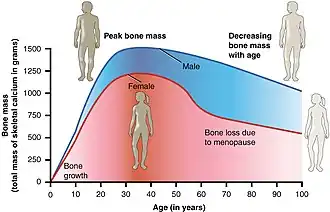

Osteoporosis may be due to lower-than-normal maximum bone mass and greater-than-normal bone loss. Bone loss increases after menopause in women due to lower levels of estrogen, and after andropause in older men due to lower levels of testosterone.[10] Osteoporosis may also occur due to several diseases or treatments, including alcoholism, anorexia or underweight, hyperparathyroidism, hyperthyroidism, kidney disease, and after oophorectomy (surgical removal of the ovaries). Certain medications increase the rate of bone loss, including some antiseizure medications, chemotherapy, proton pump inhibitors, selective serotonin reuptake inhibitors, glucocorticosteroids, and overzealous levothyroxine suppression therapy. Smoking and sedentary lifestyle are also recognized as major risk factors.[3] Osteoporosis is defined as a bone density of 2.5 standard deviations below that of a young adult. This is typically measured by dual-energy X-ray absorptiometry (DXA or DEXA).[4]

The three main mechanisms by which osteoporosis develops are an inadequate peak bone mass (the skeleton develops insufficient mass and strength during growth), excessive bone resorption, and inadequate formation of new bone during remodeling, likely due to mesenchymal stem cells biasing away from the osteoblast and toward the marrow adipocyte lineage.[107] An interplay of these three mechanisms underlies the development of fragile bone tissue.[37] Hormonal factors strongly determine the rate of bone resorption; lack of estrogen (e.g., as a result of menopause) increases bone resorption, as well as decreases the deposition of new bone that normally takes place in weight-bearing bones. The amount of estrogen needed to suppress this process is lower than that normally needed to stimulate the uterus and breast gland. The α-form of the estrogen receptor appears to be the most important in regulating bone turnover.[37] In addition to estrogen, calcium metabolism plays a significant role in bone turnover, and deficiency of calcium and vitamin D leads to impaired bone deposition; in addition, the parathyroid glands react to low calcium levels by secreting parathyroid hormone (parathormone, PTH), which increases bone resorption to ensure sufficient calcium in the blood. The role of calcitonin, a hormone generated by the thyroid that increases bone deposition, is less clear and probably not as significant as that of PTH.[37]

Trabecular bone (or cancellous bone) is the sponge-like bone in the ends of long bones and vertebrae. Cortical bone is the hard outer shell of bones and the middle of long bones. Because osteoblasts and osteoclasts inhabit the surface of bones, trabecular bone is more active and is more subject to bone turnover and remodeling. Not only is bone density decreased, but the microarchitecture of bone is also disrupted. The weaker spicules of trabecular bone break ("microcracks") and are replaced by weaker bone. Common osteoporotic fracture sites, the wrist, the hip, and the spine, have a relatively high trabecular bone to cortical bone ratio. These areas rely on the trabecular bone for strength, so the intense remodeling causes these areas to degenerate most when the remodeling is imbalanced. Around the ages of 30–35, cancellous or trabecular bone loss begins. Women may lose as much as 50%, while men lose about 30%.[39]

Osteoporosis becomes more common with age, especially after 50 years (its prevalence rises from about 2% at 50 years to almost 50% by the age of 80).[200] It affects women more than men due to the sharp fall in estrogen production that follows menopause.[200] Globally, it is estimated that 21.2% of women and 6.3% of men over the age of 50 have osteoporosis, corresponding to a total of around 500 million people worldwide.[201] About 15% of Caucasians in their 50s and 70% of those over 80 are affected.[7] In the developed world, depending on the method of diagnosis, 2% to 8% of males and 9% to 38% of females are affected.[13] Rates of disease in the developing world are unclear.[14]

From the age of 50 onwards, fractures (including hip fractures) are roughly twice as common in women than in men.[202] A 60-year-old woman has a 44% chance of experiencing a fracture in her lifetime, whereas the lifetime risk for a 60-year-old man is only 25%.[203] Such differences can be attributed to the increased risk of osteoporosis due to decreased estrogen levels following menopause.[203]